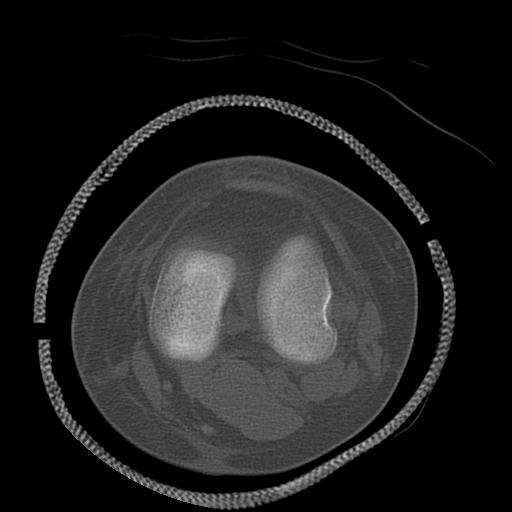

100612 11/25 1/20 右膝 2R 84歳女性 右TKA